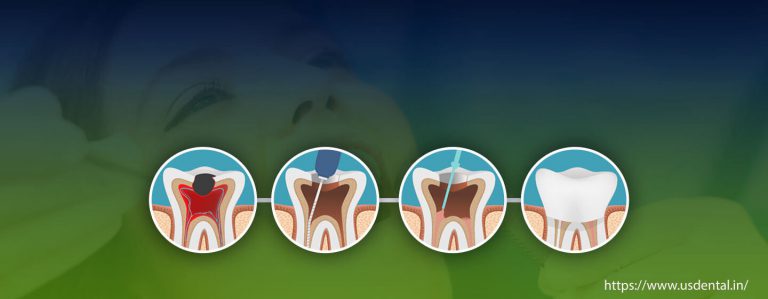

Case of the month: Root Canal Treatment Middle age women reported to the US DENTAL CLINIC with a chief complaint…

WHAT IS A SINGLE VISIT ROOT CANAL TREATMENT? AM I A CANDIDATE FOR IT? Mostly we all have experienced the…

Common Questions Answered About Root Canal Treatment Some people might have questions in mind before booking a dental appointment whether…